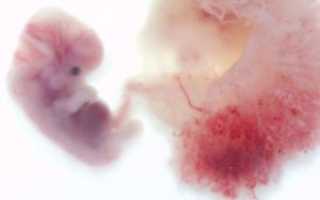

В начале беременности плод растет буквально «не по дням, а по часам». На пятой неделе, он уже успел превратиться из шарообразного плодного яйца в эмбрион, напоминающий своим внешним видом головастика.

Если срок беременности пять недель, то размер плода сравним с зернышком риса. Его вес немногим более одного грамма, а размер – около трех миллиметров.

Если срок беременности уже пять недель, то на месте шарообразного плодного яйца уже успел сформироваться эмбрион. Внешне он похож на диск, разделенный полоской пополам. Эта полоска – ось симметрии тела будущего человечка, то есть, будущий позвоночник. На этом сроке плод уже имеет зачатки некоторых внутренних органов. У него начинают формироваться системы дыхания и пищеварения.

Если контур плодного яйца напоминал шарик, то плод на пятой неделе можно сравнить с полумесяцем или буквой С. У него уже можно различить место, где будет формироваться голова.

Размер ребёнка составляет 4-5 мм. У эмбриона начинают формироваться органы. Изо дня в день развитие усложняется. В начале недели у ребёнка сформируется нервная трубка — основа для процесса развития центральной нервной системы. Она находится по длине всего организма эмбриона и даёт возможность развиться головному и спинному мозгу.

На 5 неделе беременности организм будущего ребенка продолжает свое бурное развитие. В беспорядочном, казалось бы, делении клеток появляется определенная система и уже можно под микроскопом различить зачатки отдельных частей тела.

Ваш малыш теперь напоминает головастика. Поразительно, но у него уже начинают формироваться реагирующие на свет глазки и ноздри, а также развивается сердечко. Кстати, если вы ждете мальчишку, то у него уже закладываются зачатки семенников, практически сразу начинающие производить тестостерон. Ваши яичники продолжают вырабатывать гормон прогестерон, который поддерживает беременность.